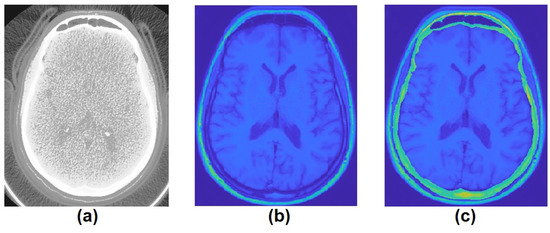

2.2. Data Processing I

2.3. Data Processing II